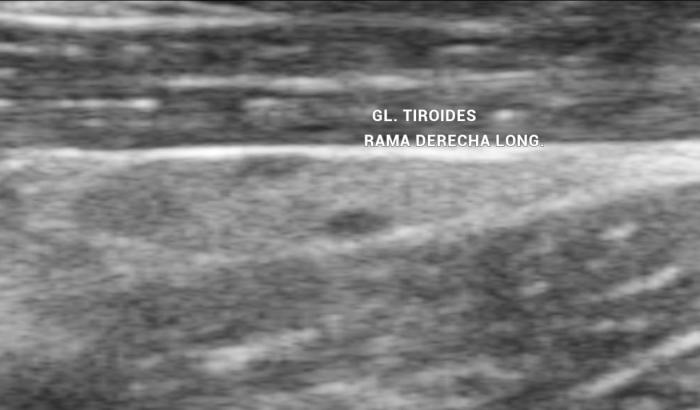

La glándula tiroides en perros y gatos está constituida por dos lóbulos situados a ambos lados de la tráquea cervical, con disposición longitudinal y una forma fusiforme o alargada que se extiende desde el cartílago cricoides hasta la entrada torácica superior2. En condiciones normales, cada lóbulo presenta contornos bien definidos, cápsula hiperecogénica delgada y parénquima homogéneo, con una ecogenicidad generalmente igual o ligeramente superior al músculo esternohioideo adyacente3,8. En la imagen transversal, los lóbulos suelen adoptar una configuración oval o ligeramente triangular (Figura 1); en longitudinal, se observa una forma alargada con extremos redondeados y orientación paralela a los vasos carotídeos y la tráquea1 (Figura 2).

En cuanto a los parámetros ecográficos de referencia, estudios realizados en perros han determinado que los lóbulos tiroideos sanos presentan una longitud entre 13-23 mm, ancho de 3-8 mm y alto de 2-5 mm, con variaciones según raza y tamaño corporal6. En gatos, las dimensiones normales son más pequeñas y oscilan entre 10-17 mm de largo, y 2-4 mm de ancho y alto, dependiendo de la edad y el estado funcional10 (ver además la Tabla 1).